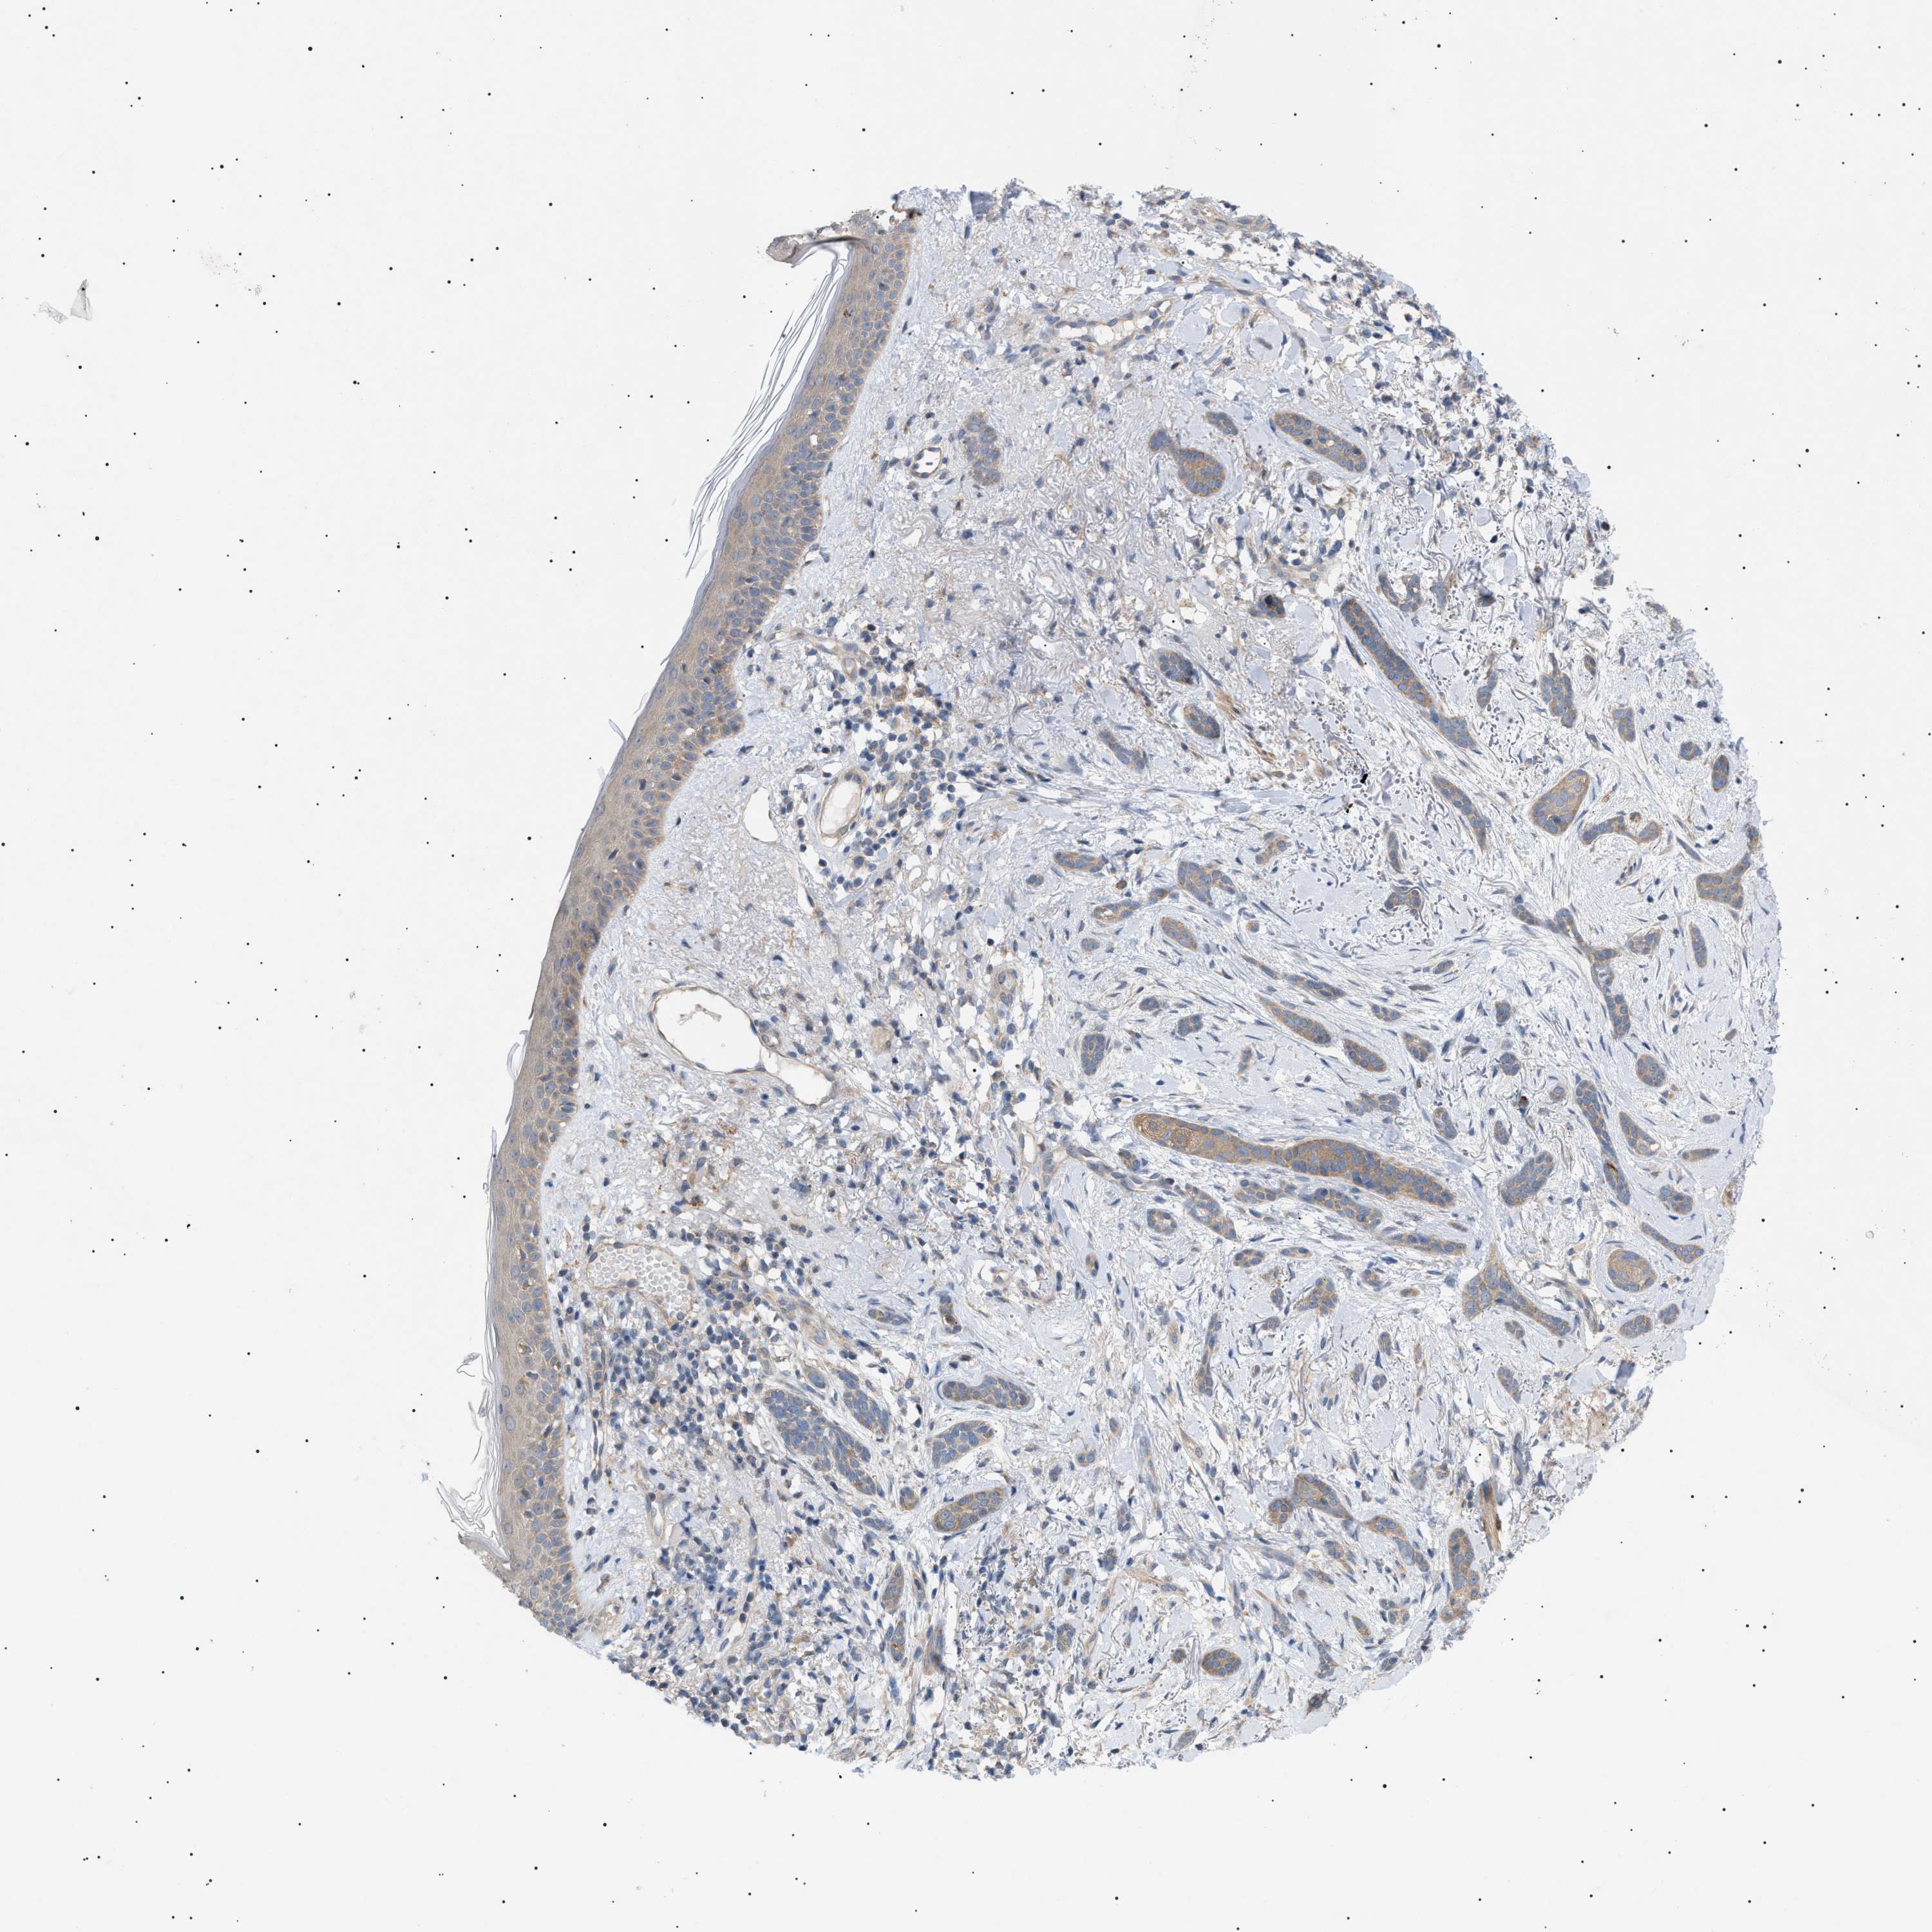

Basal cell and squamous cell cancer

SKIN CANCER - Protein expressioni

A mouse-over function shows sample information and annotation data. Click on an image to view it in a full screen mode. Samples can be filtered based on level of antibody staining by selecting one or several of the following categories: high, medium, low and not detected. The assay and annotation is described here.

Note that samples used for immunohistochemistry by the Human Protein Atlas do not correspond to samples in the TCGA dataset.

Antibody stainingi

Antibody staining in the annotated cell types in the current human tissue is reported as not detected, low, medium, or high, based on conventional immunohistochemistry profiling in selected tissues. This score is based on the combination of the staining intensity and fraction of stained cells.

Each image is clickable and will lead to virtual microscopy that enables deeper exploration of all samples and also displays staining intensity scores, fraction scores and subcellular localization as well as patient and tissue information for each sample.

Antibody CAB016944

Staining

High

Medium

Low

Not detected

Intensity

Strong

Moderate

Weak

Negative

Quantity

>75%

75%-25%

<25%

None

Location

Nuclear

Cytoplasmic/membranous

Cytoplasmic/membranous,nuclear

Squamous cell carcinoma in situ, NOS

Squamous cell carcinoma, NOS

Squamous cell carcinoma, metastatic, NOS

Basal cell carcinoma

Adnexal tumor, benign